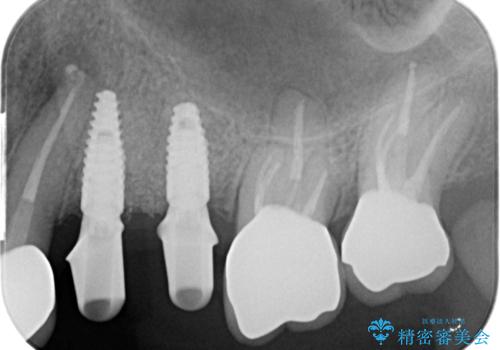

長期的な予後を見込むことが難しいため、相談の上抜去を行いインプラント治療を進めていくこととなりました。

- 123.2万円(インプラント×2・チタンカスタムアバットメント×2・ジルコニアクラウン×4・仮歯×4)費用は治療当時の料金となります